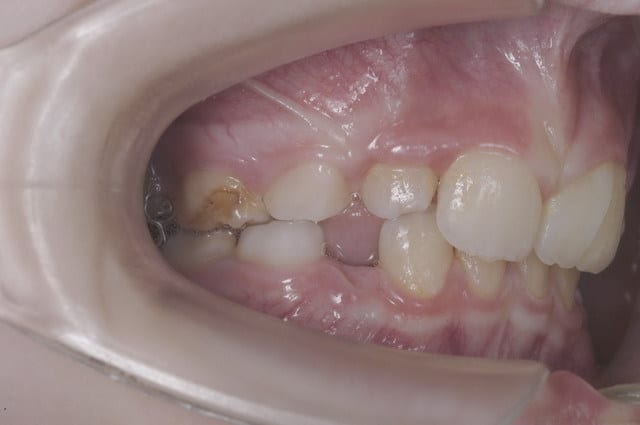

J'ai vu il y a 2 mois un enfant de 8ans qui présente une 21 double et dont la racine semble unique.L'enfant présentant une birétroalvéolie incisive et une supraclusie l'ortho aimerait savoir ce qui serait deja possible de faire pour réduire la taille de la couronne compte tenu de la taille de la racine.

Ci joint le pano du cas de gémination de 21 du petit Cham.

quitte a paraitre déphasé, une simple retro alveolaire, bien de face et montrant bien la racine m'irait bien, ce n'est pas une critique, ton truc est bien exposé

dans ta belle presentation du cas je trouve que ça me manque un peu, on ne voit pas l'anatomie de cette racine, on la devine mais tres mal, pourtant je trouve que c'est un élément primordial

La rétro se trouve dans le 2ème message (Cham2 jpg)